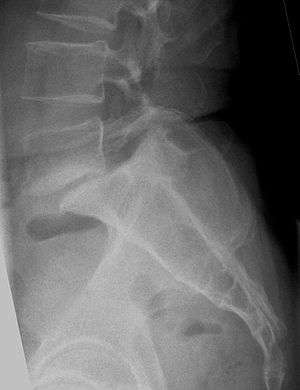

Lumbar vertebra showing central stenosis and lateral recess stenosis.

Normal lumbar vertebra showing large, round spinal canal.

The diagnosis is based on clinical findings.[6] Some patients can have a narrowed canal without symptoms, and do not require therapy. Stenosis can occur as either central stenosis (the narrowing of the entire canal) or foraminal stenosis (the narrowing of the foramen through which the nerve root exits the spinal canal). Severe narrowing of the lateral portion of the canal is called “lateral recess stenosis". The ligamentum flavum (yellow ligament), an important structural component intimately adjacent to the posterior portion of the dural sac (nerve sac) can become thickened and cause stenosis. The articular facets, also in the posterior portion of the bony spine can become thickened and enlarged causing stenosis. These changes are often called “trophic changes” or “facet trophism” in radiology reports. As the canal becomes smaller, resembling a triangular shape, it is called a "trefoil" canal.

The normal lumbar central canal has a midsagittal diameter (front to back) greater than 13 mm., with an area of 1.45 square cm. Relative stenosis is said to exist when the anterior-posterior canal diameter measures between 10 and 13 mm. Absolute stenosis of the lumbar canal exists anatomically when the anterior-posterior measurement is 10 mm. or less.[11][12][13]